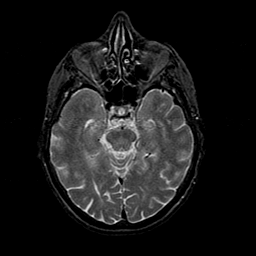

Normal aging, overlay -- Slice #20

[Home][Help][Clinical] Slice 20